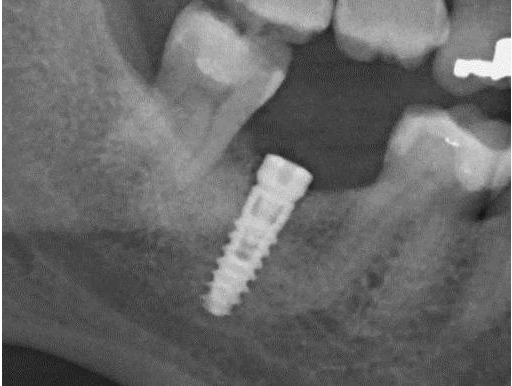

Ασθενής ετών 57 προσήλθε στο ιατρείο παραπονούμενος για ήπιο πόνο, φλεγμονή και πυορροή στο εμφύτευμα που είχε τοποθετηθεί προ τριετίας. Κλινικά και ακτινογραφικά διαπιστώθηκε οστική απώλεια γύρω από το εμφύτευμα (οστική βλάβη- κρατήρας). Ακολούθησε χειρουργική διάνοιξη στην περιοχή, καθαρισμός του εμφυτεύματος, τοποθέτηση οστικού μοσχεύματος και μεμβράνης (οστική ανάπλαση).

Έξι μήνες μετά κλινικά η βλάβη έχει επαλειφθεί και ακτινογραφικά εμφανίζεται οστική πλήρωση αυτής.

Περιεμφυτευματική βλάβη - Αρχική Ακτινογραφία

Περιεμφυτευματική βλάβη - Τελική Ακτινογραφία